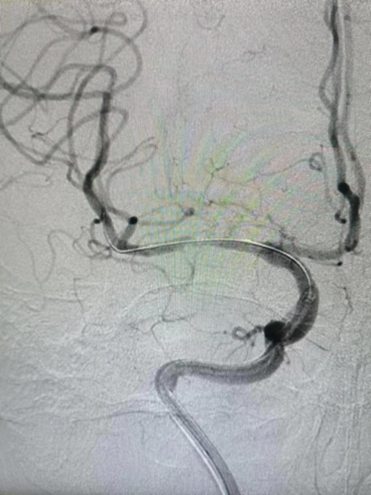

术后影像及检查

术后正位造影。

术后侧位造影